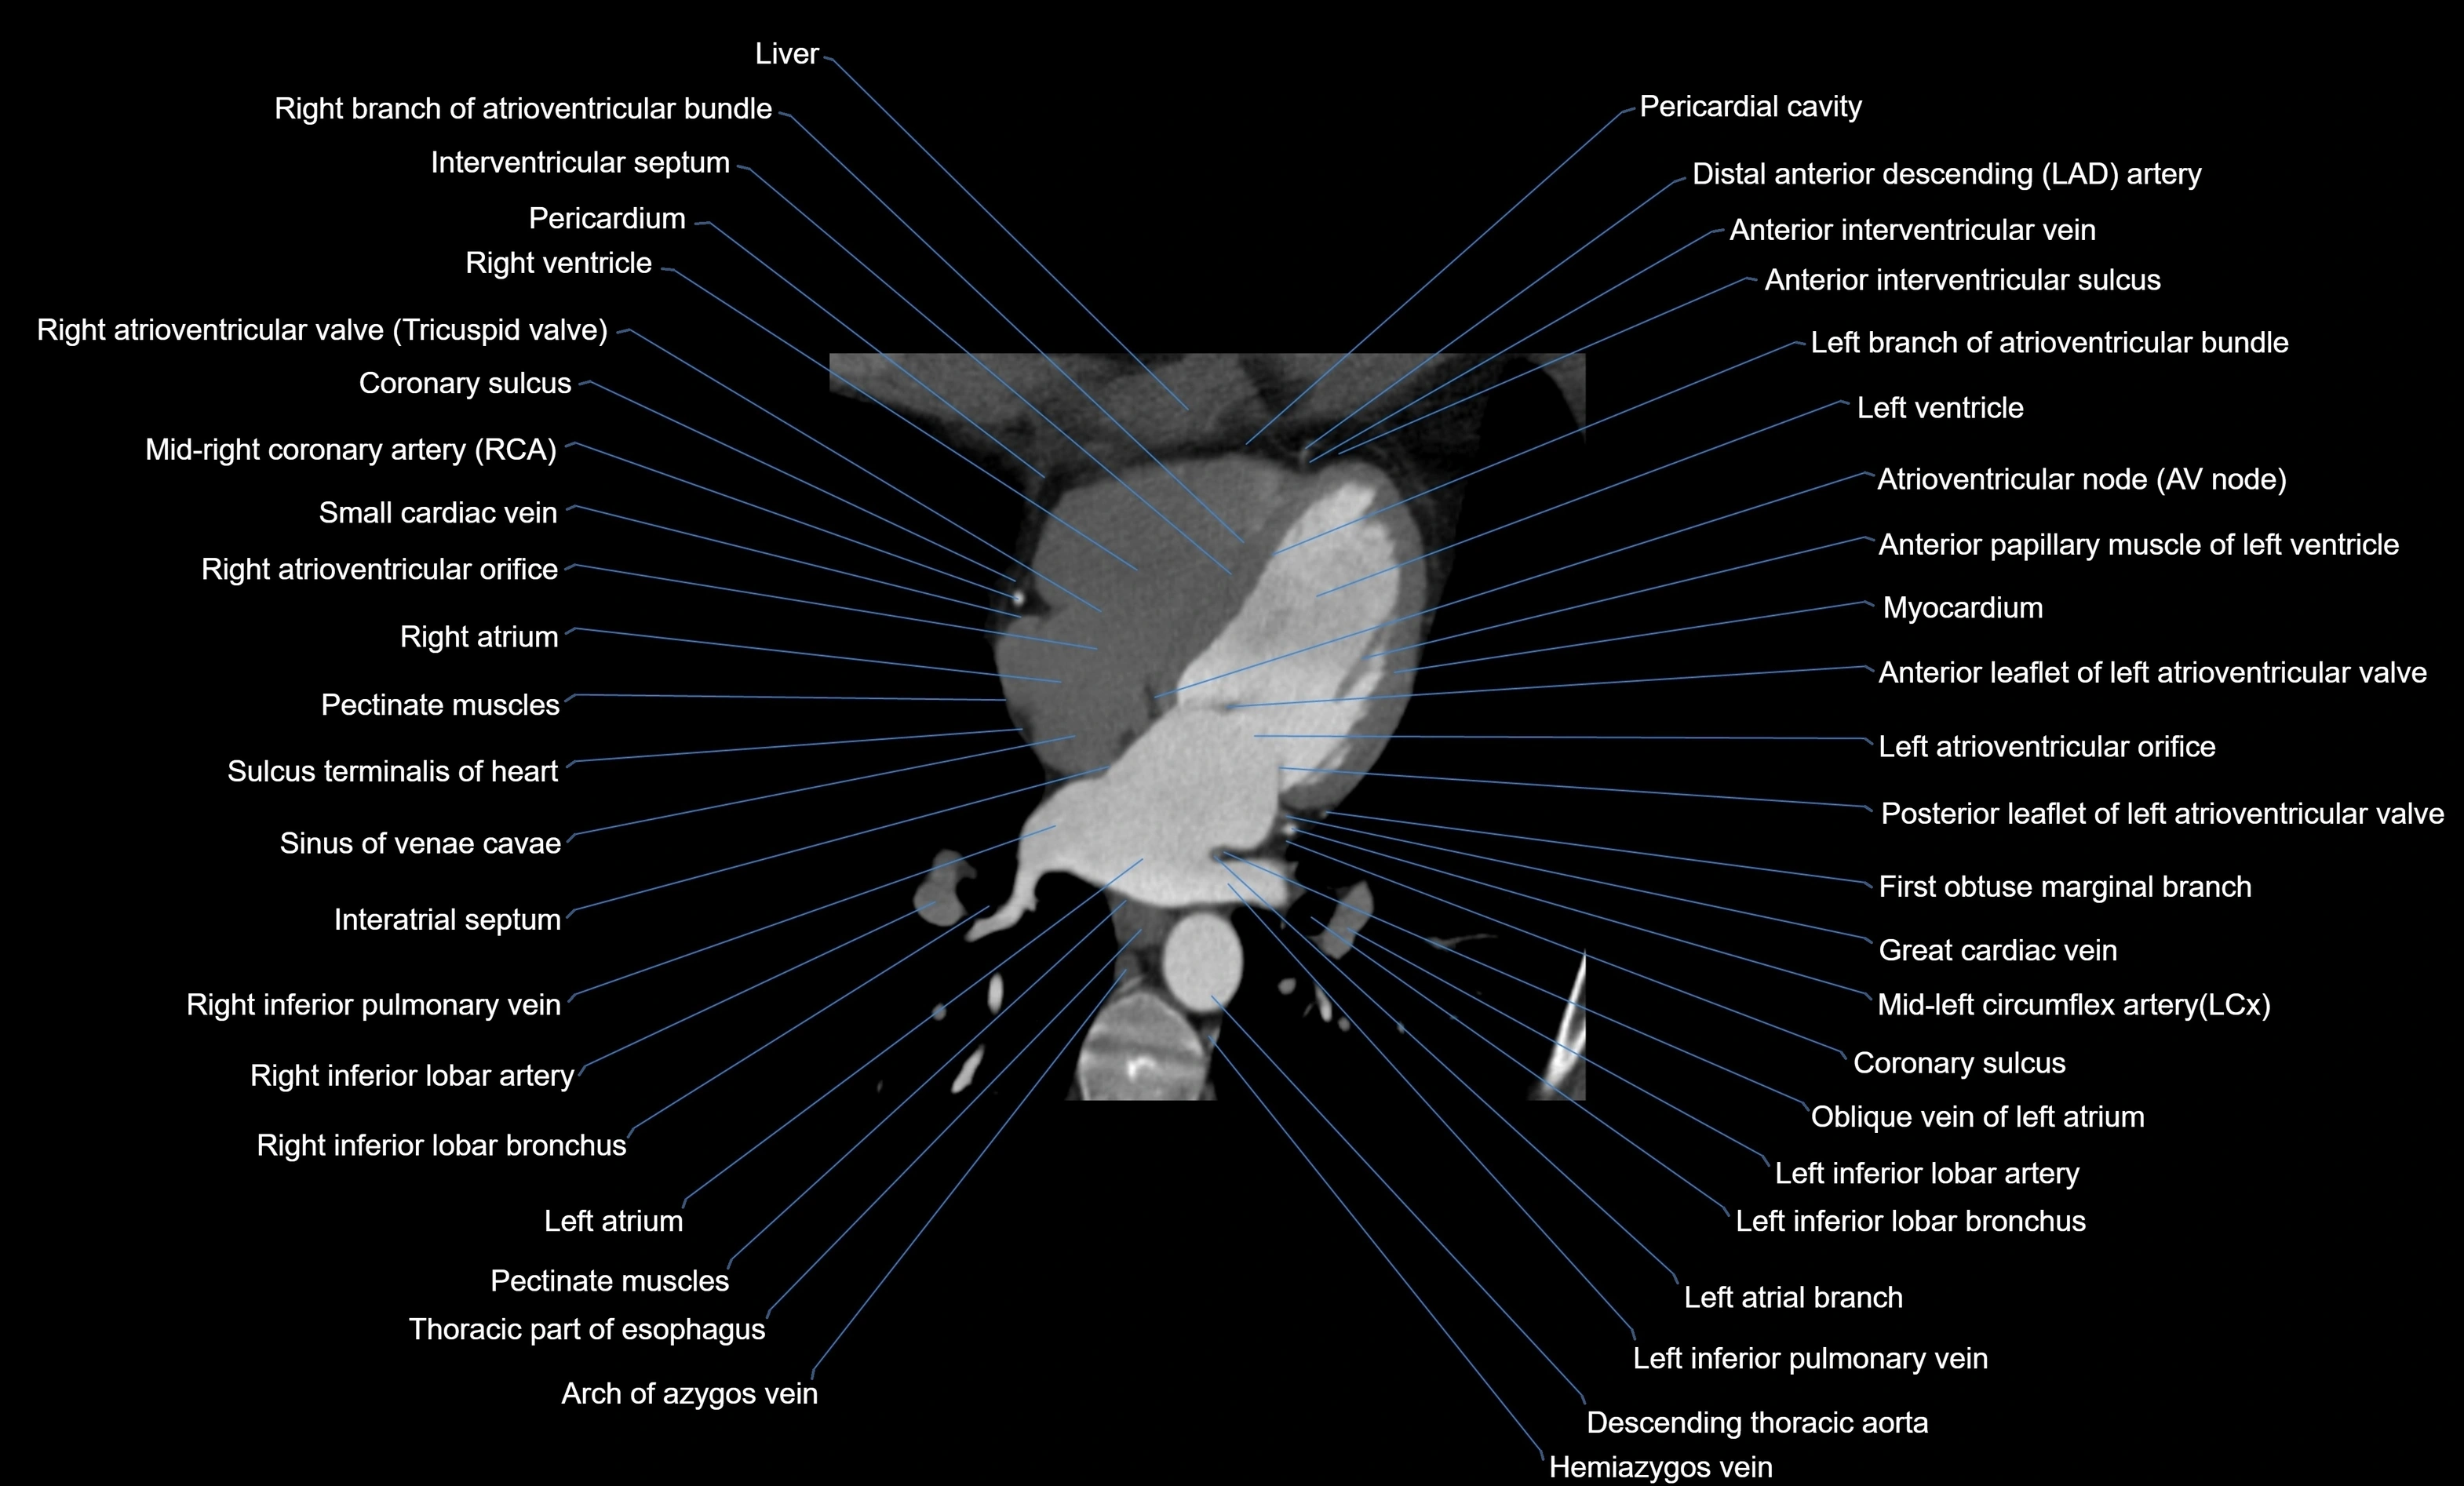

- Anterior interventricular sulcus

- Anterior leaflet of left atrioventricular valve

- Atrioventricular Node (AV Node)

- Azygos vein

- Coronary sulcus

- Descending thoracic aorta

- Distal left anterior descending artery (dLAD)

- First obtuse marginal branch

- Great cardiac vein

- Interatrial septum

- Interventricular Septum

- Left anterior descending artery (LAD)

- Left atrioventricular valve (mitral or bicuspid valve)

- Left atrium

- Left branch of atrioventricular bundle

- Left ventricle

- Middle cardiac vein

- Oblique vein of left atrium

- Pericardial cavity

- Pericardium

- Posterior leaflet of left atrioventricular valve

- Right atrioventricular valve (tricuspid valve)

- Right atrium

- Right branch of atrioventricular bundle

- Right inferior pulmonary vein

- Right ventricle

- Sinus of venae cavae (sinus venarum)